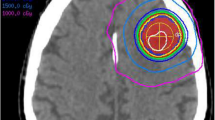

2D distortion-corrected MRIs had been used for treatment planning in 52.5% (220/419) of lesions, while uncorrected MRIs had been employed in the remaining 47.5% (199/419) of metastases. No instance of 3D distortion correction was identified in the present series. Figure 1 shows four exemplary brain metastases cases from the uncorrected subgroup with pronounced distortions.

Exemplary cases from the uncorrected subgroup with considerable distortions. Uncorrected MR images are shown overlaid by uncorrected and corrected GTV contours. Red contours depict the uncorrected GTV perimeter, green contours display the corrected tumor outline after 3D distortion correction for gradient nonlinearity-induced distortions.